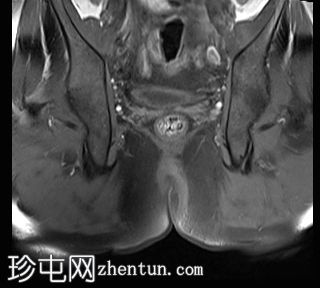

冠状位

T2

位于5点钟和6点钟位置之间,在STIR和T2加权图像上呈高信号。

瘘管起源于括约肌间平面附近,穿过肛门内外括约肌,并延伸至左侧坐骨肛门窝。瘘管内充满液体信号,周围有轻微水肿。肛提肌上方未观察到颅骨延伸。

根据圣詹姆斯大学医院的磁共振分类系统,该病例被归类为III级左侧肛周经括约肌瘘,左侧坐骨肛门窝可见炎症改变。